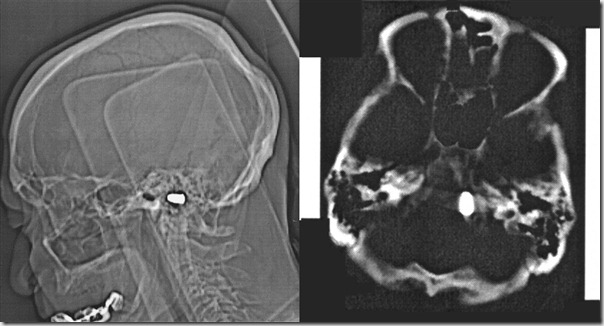

Каково было их удивление, найти прямо у основания черепа рядом с “foramen magnum” (радиологи меня поправят) настоящую пулю.

Courtesy of Maya Safarova, M.D. and Marat Ezhov, M.D., Ph.D.

Оказывается, когда пациенту было три года, в него случайно выстрелил его брат. Причем ни куда-нибудь, а прямо в голову. Пуля вошла в область ноздри и уже никогда не выходила.

Ровно 82 года назад, хирурги отказались оперировать ребенка сославшись на возможные не обратимые осложнения.

Как мы видим сегодня, человек прожил с пулей в голове 82 года. Он сделал успешную карьеру инженера и дожил до преклонных лет.

Случай уникальный, пуля не задела и в последствии не сдавила, ни один из жизненно-важных центров.

Решение врачей сегодняшних дней, повторяет заключение 82-х летней давности: “пулю не вынимать”, с единственной оговоркой: МРТ противопоказан.